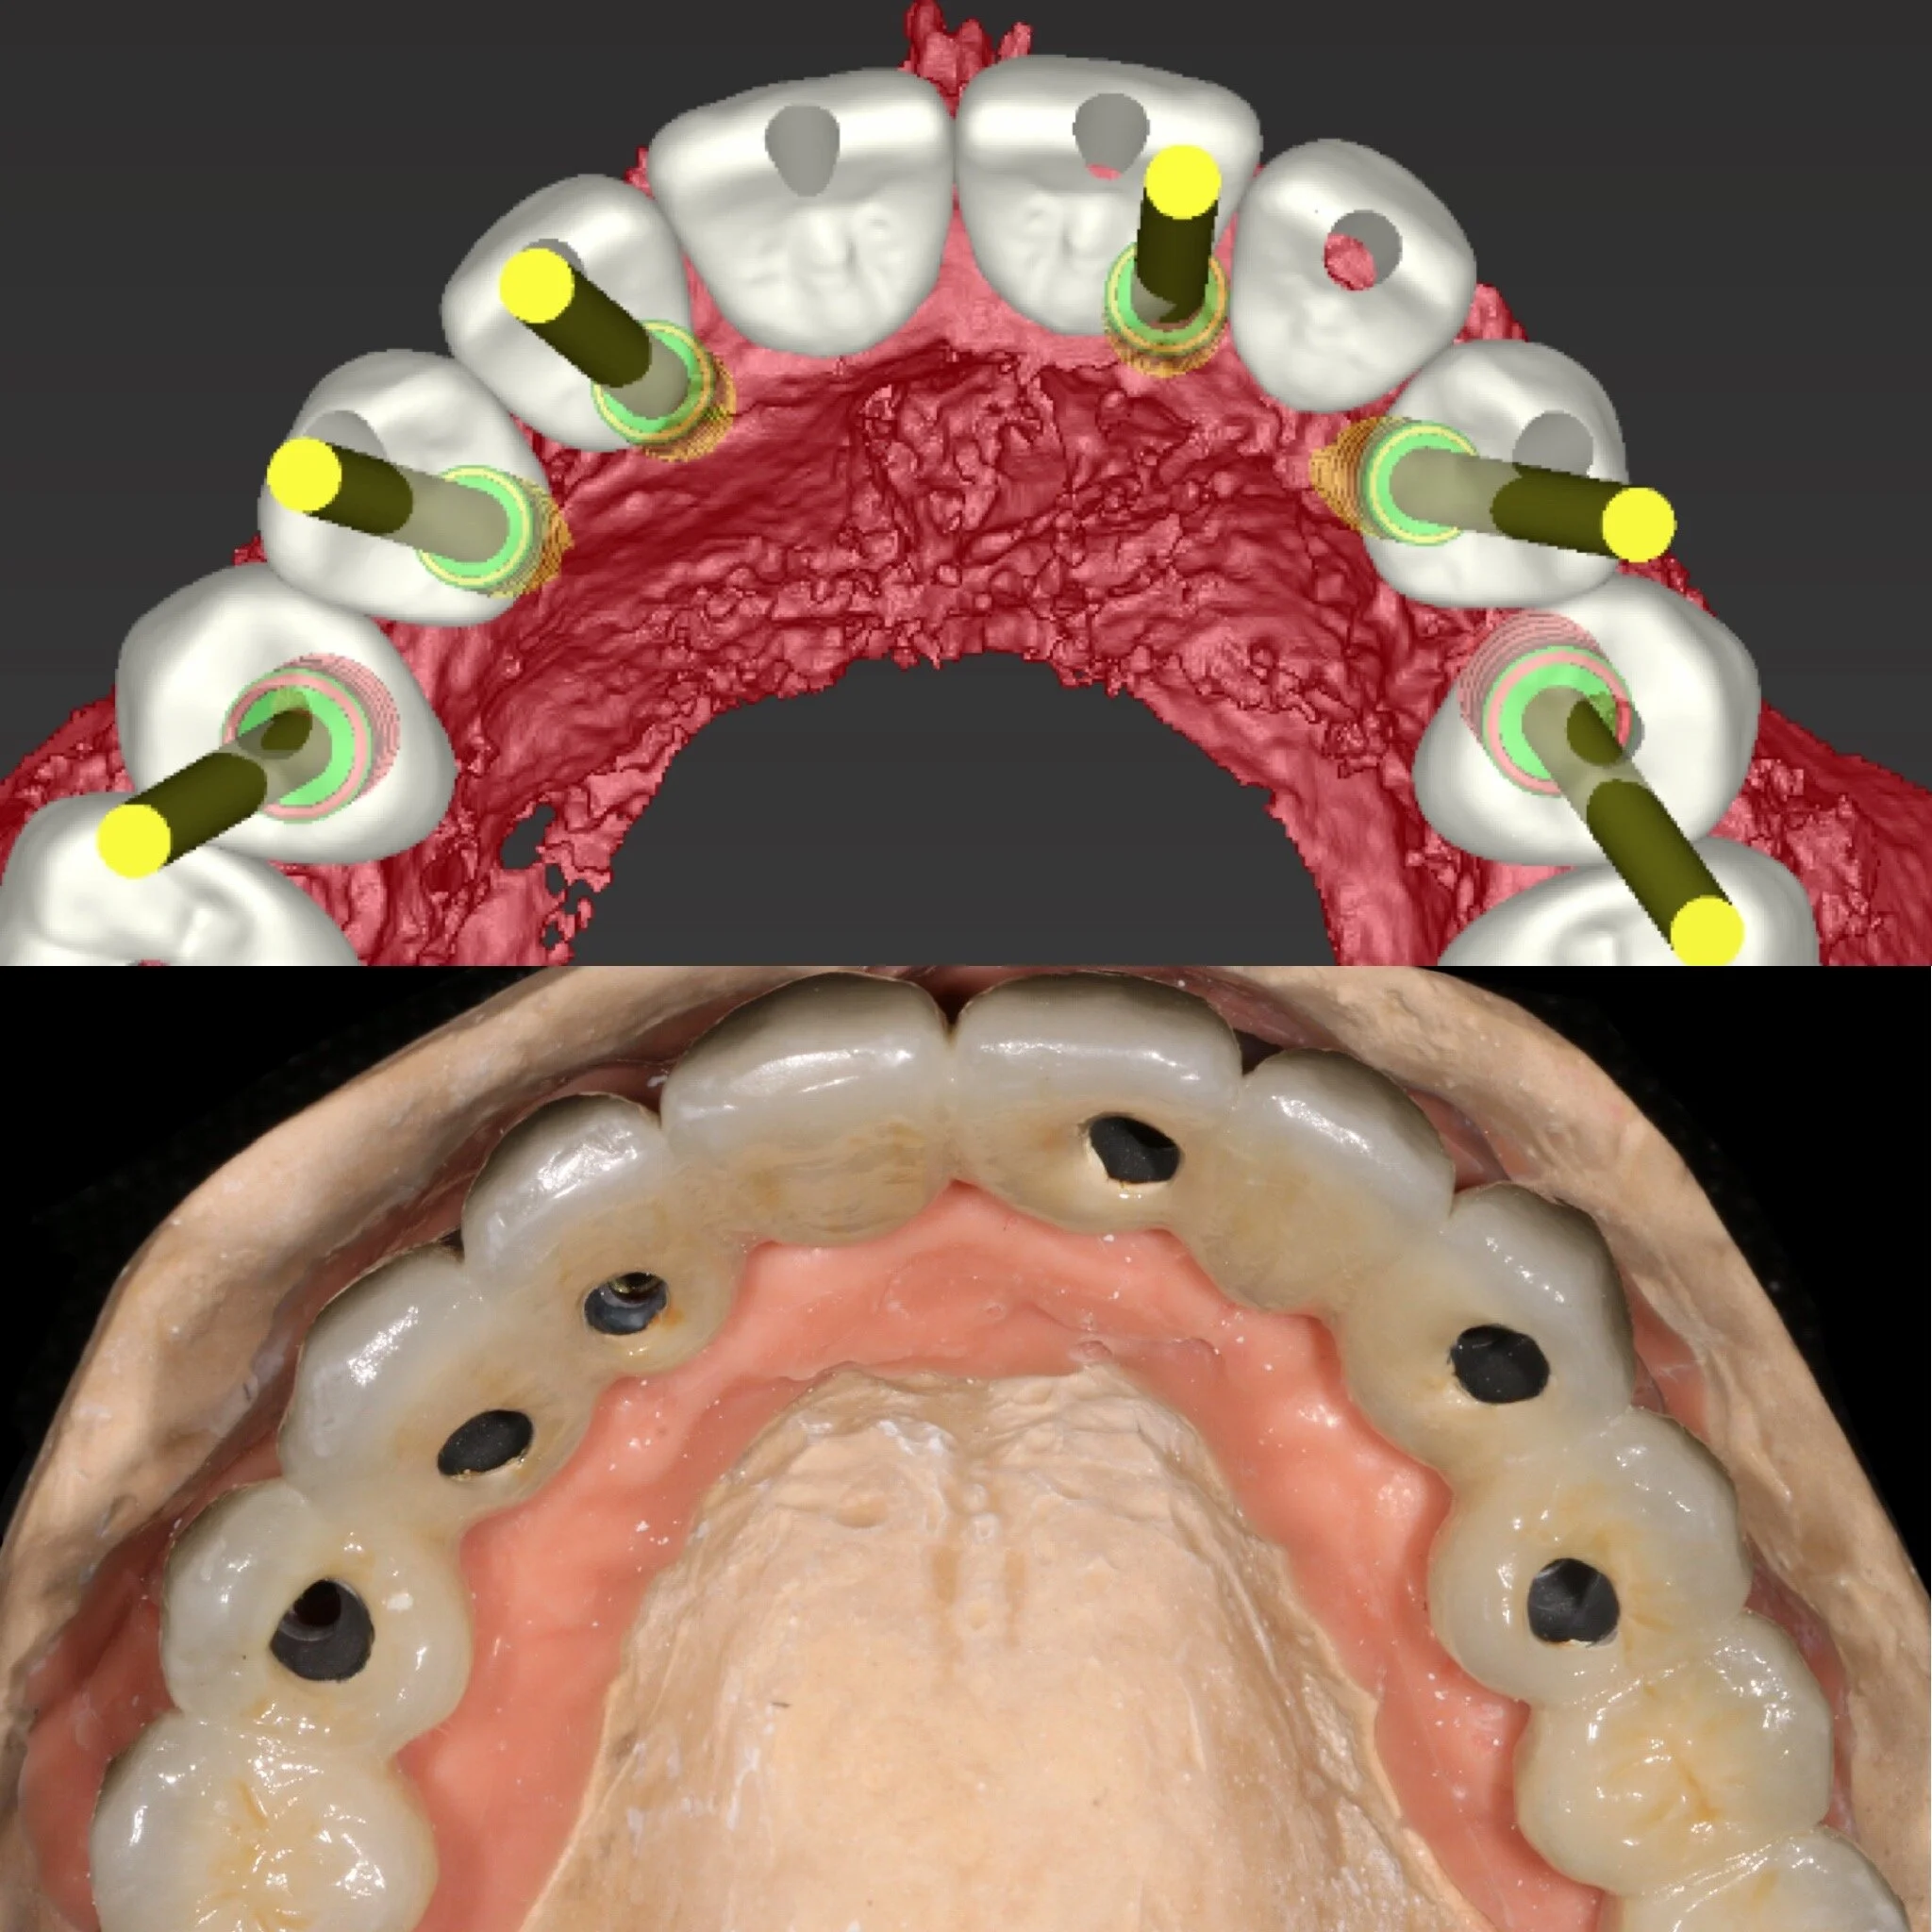

Utredningen kommer sedan att stå som en biologisk grund för Din behandling där faktorer som allmänhälsa, oral hälsa, mediciner, mjukvävnad m.m kommer att studeras. Benvolym utvärdeas med hjälp av avancerad röntgenteknik som avbildar käkarna i 3D. Bilden förs sedan över till ett datorprogram där Dr. Osama planerar behandlingen utifrån Dina förutsättningar. På så sätt kan implantaten placeras med mycket hög precision och kvalitet. Detta för att ge Dig ett resultat som både är biologiskt, funktionellt och anpassat efter just Dina förväntningar/önskemål.